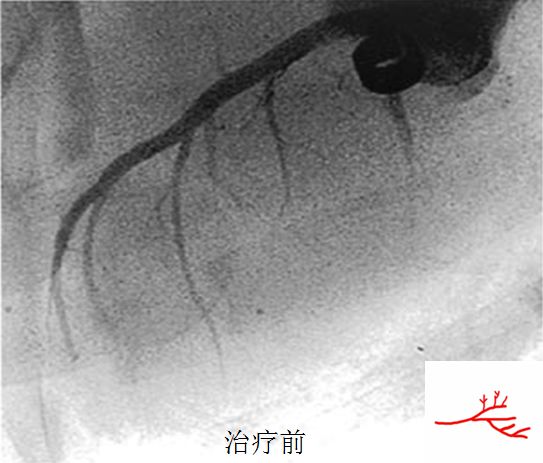

CSWT是利用超声定位,依靠心电图门控技术触发,通过仪器下端的水垫及超声耦合剂,向设定的心脏治疗靶区域释放脉冲式声能量(震波),以抑制缺血相关的细胞损伤,促进缺血区域的毛细血管生成、微循环重建。